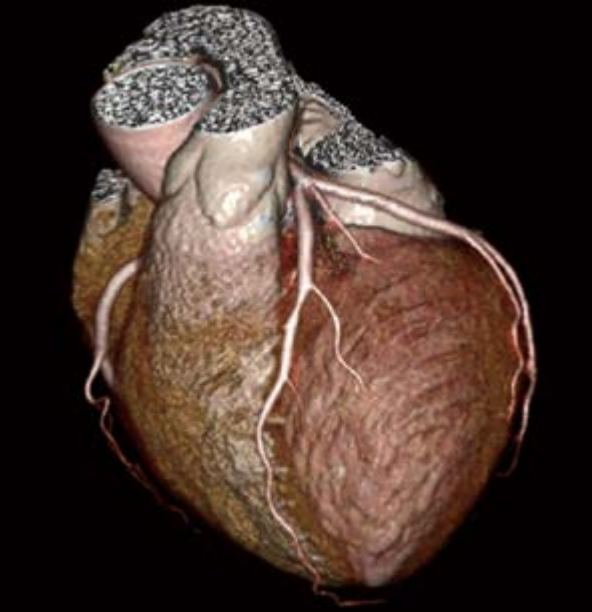

SinoVision Insitum 64s - это 64 срезовый КТ с большой апертурой гентри 75см. Один из самых доступных кардиологических компьютерных томографов. SinoVision Insitum 64 - это 64 срезовый КТ с большой апертурой гентри 76см. Уникальная интеллектуальная система управления стробированием SinoVision и алгоритм реваскуляризации коронарных артерий гарантируют мгновенное замораживание сердца и отображение структуры сердечно-сосудистой системы, стента, кальцификации, бляшек и другой информации в высоком разрешении.

- Интеллектуальная платформа коронарной визуализации мгновенно замораживает сердце и отображает информацию высокого разрешения о сердечно-сосудистых структурах, стентах, кальцификации и бляшках с помощью уникальной интеллектуальной системы управления и алгоритмов коронарной реваскуляризации SinoVision.

- Изображения процесса замораживания коронарной артерии в режиме реального времени

- Управление стробированием на основе модуляции в реальном времени - Система управления модуляцией синхронизации - Редактирование ЭКГ - Автоматический захват фазы - Отображение данных дыхательной волны - Встроенная система управления синхронизацией - Интеллектуальная аналитическая платформа

- Расширенный коронарный анализ

- Определяет степень стеноза и состав бляшки коронарной артерии, помогает при послеоперационном осмотре при шунтировании и стентировании